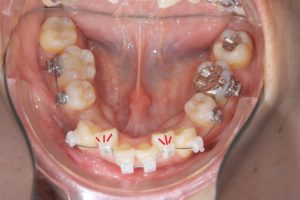

他にも

前突を伴わない重度叢生の症例でも

抜歯してスペースを確保することがあります。

治療前

第一小臼歯抜歯後1カ月経過。

中切歯と犬歯の間にオープンコイルを入れ

側切歯のスペース作り開始。

抜歯後5カ月経過。側切歯にブラケット装着。

抜歯後10カ月経過。舌側にリンガルボタンを装着。

パワーチェーンを使ってスペース閉鎖中。

前歯にスペースが開かないように、犬歯~犬歯を連続結紮。

このような重度叢生の場合も抜歯して作った

スペースを利用しレベリングをするケースもあります。